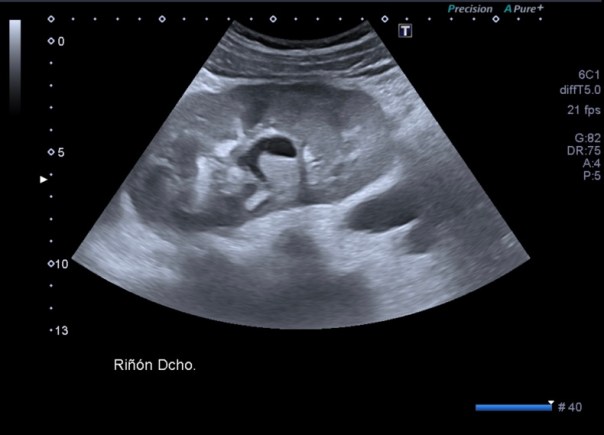

Lesión heterogénea, en el meso-riñón derecho, redonda, típica de quiste hidatídico.

Un quiste hidatídico renal, maravilloso.